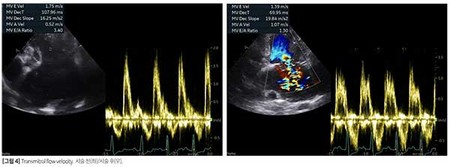

좌심방 압력 상승 관련 지표는 시술 전보다 개선되었으나(E peak 1.36->1.19m/s, E/Em 12.23->10.95, E/IVRT 3.15->1.83, [그림 3]) 삼첨판 역류량이 중-심등도로 증가했고, 수축기 폐동맥압은 97mmHg 이상으로 뚜렷하게 상승해 우심 부전 발생 가능성이 높은 것으로 평가됐다.

좌심방 감압술은 [증례 1]과 동일한 방식으로 진행됐다. 시술 후 10일 차 재검에서 좌심방 압력 상승 관련 지표는 여전히 좋지 않았지만(E peak 1.75->1.39m/s, E/Em 20.19->18.92, E/IVRT 5.42->2.14) 시술 전과 비교 시 개선된 양상을 보였다[그림 4].